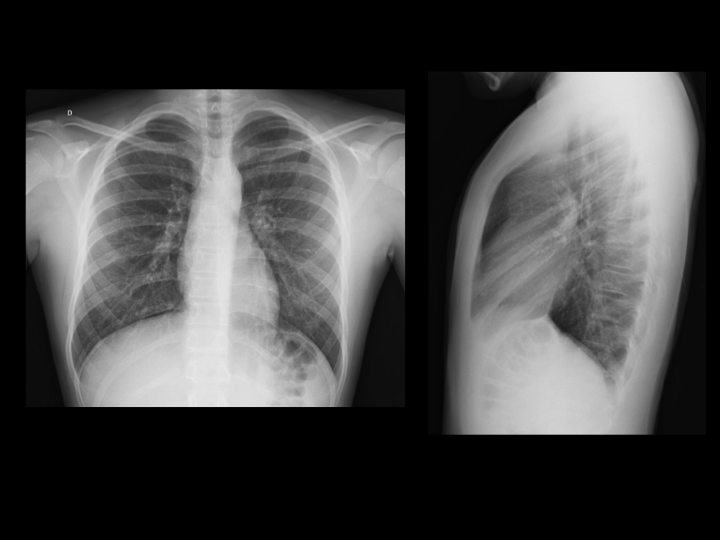

- Incidência posteroanterior (PA): é a principal incidência de todas as radiografias. O paciente fica em pé em frente ao equipamento e a imagem é tirada com os raios passando pelas costas e saindo pela frente do tórax. Caso esteja acamado, ela deverá ser substituída pela AP (anteroposterior), apesar dessa apresentar mais distorções anatômicas.

- Perfil: paciente fica de lado e os raios passam perpendicularmente à máquina. Essa incidência permite uma boa avaliação retroesternal e é sensível para pequenos derrames pleurais